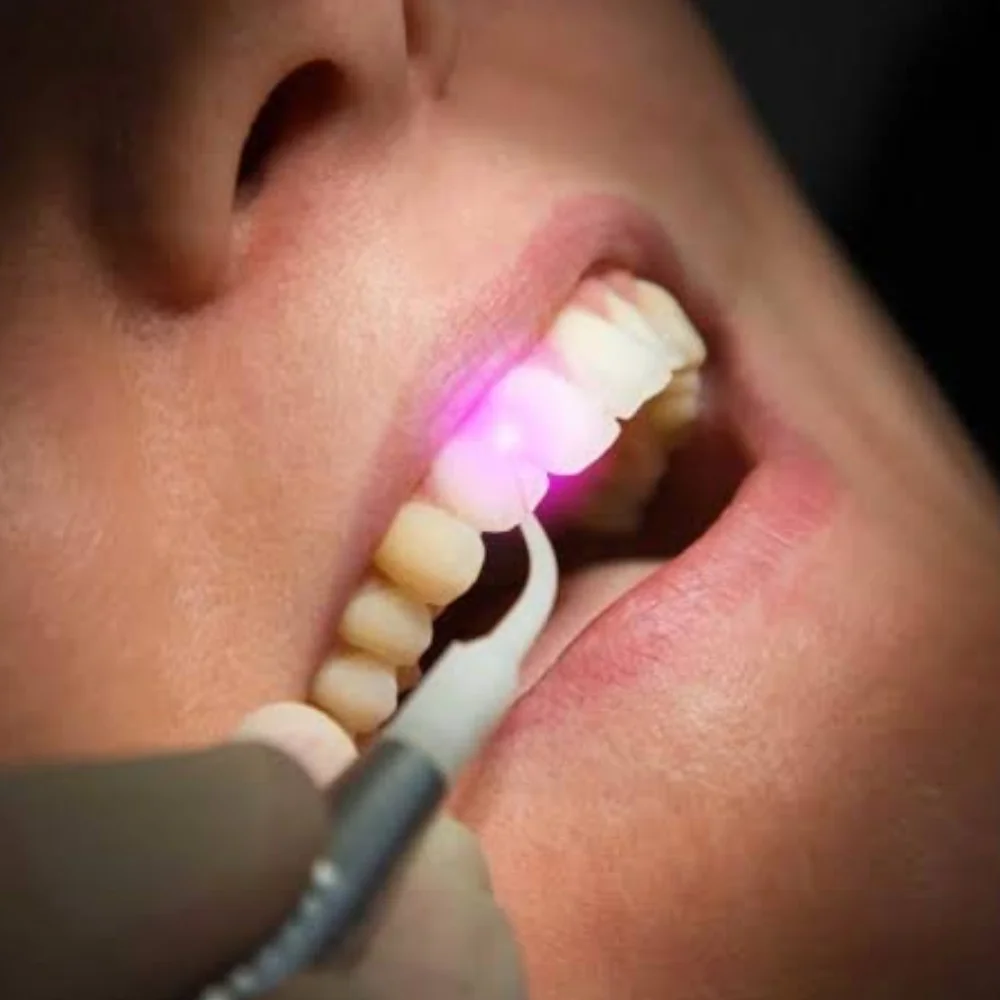

Laser Dentistry

Advanced Laser Therapy for Healthier Gums and a Brighter Smile

At GS Dental Care, we specialize in providing exceptional dental laser treatments using state-of-the-art technology, ensuring that you receive the best possible care. Laser dentistry is a minimally invasive treatment for addressing periodontal and gum issues, crown lengthening, and laser-assisted teeth procedures.

Laser Periodontal Therapy

Treats gum disease by removing bacteria and infected tissue.

Laser Frenectomy

Corrects tongue-tie or lip-tie with a quick and painless laser procedure.